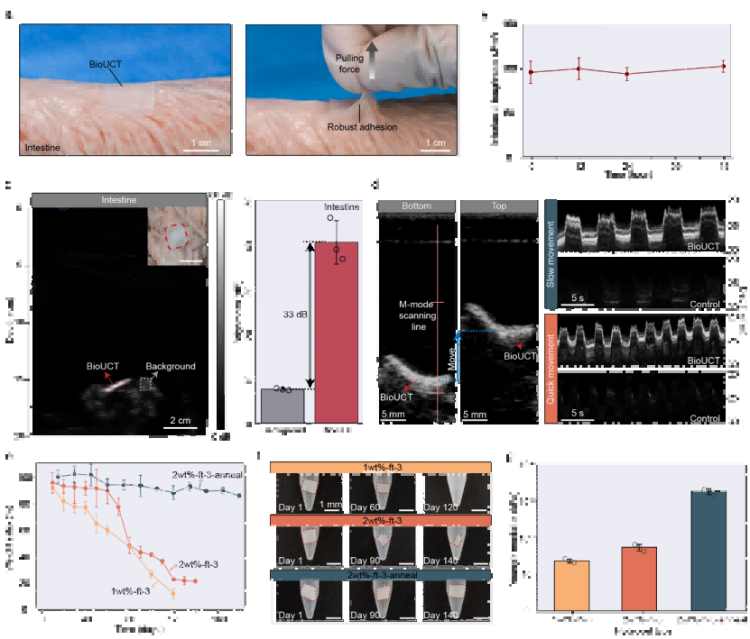

①革命性成像性能:從“看不見”到“高清追蹤”超強(qiáng)聲學(xué)反射(圖2a-b)通過(guò)周期性微氣囊設(shè)計(jì),BioUCT在體外測(cè)試的2MHz超聲下實(shí)現(xiàn)57dB頻譜信號(hào)增幅(較普通水凝膠),在實(shí)際動(dòng)物實(shí)驗(yàn)中將B超圖像亮度提升30dB,使腸道輪廓清晰顯現(xiàn)(圖2b)。時(shí)/頻域分析顯示其回聲強(qiáng)度遠(yuǎn)超軟組織(圖2a),解決了腸道超聲的信噪比受腸道“弱反射”限制的核心痛點(diǎn)。

抗形變穩(wěn)定性(圖2f-g)在50%拉伸及90°彎曲狀態(tài)下(模擬腸道蠕動(dòng)),B超/M超成像亮度波動(dòng)<5%(圖2f),相位監(jiān)測(cè)波形穩(wěn)定(圖2g),確保動(dòng)態(tài)監(jiān)測(cè)可靠性。

大角度成像能力(圖2c-e)探頭在深度(5-25cm)、角度(±30°)、水平位移(±20mm)變化時(shí),圖像亮度標(biāo)準(zhǔn)差<1.5dB(*n*=3),適配臨床操作誤差。

② 智能生物適配:像“第二層生物表皮”一樣工作強(qiáng)力粘附與抗脫落(圖3a-b)離體豬腸實(shí)驗(yàn)證實(shí),BioUCT與腸壁界面韌性達(dá)200 J/m2(相當(dāng)于外科縫合強(qiáng)度),48小時(shí)內(nèi)粘附穩(wěn)定性>95%(圖3b)。拉力測(cè)試中可承受10N以上牽拉(圖3a),遠(yuǎn)超腸道蠕動(dòng)產(chǎn)生的生理應(yīng)力(通常<2N)。

精準(zhǔn)降解調(diào)控(圖3e-g)通過(guò)調(diào)節(jié)PVA/CMC水凝膠結(jié)晶度,實(shí)現(xiàn)10%-90%的可控降解速率(120天內(nèi)),且降解過(guò)程中楊氏模量保持15-35kPa(圖3g),始終匹配軟組織力學(xué)特性,避免器官損傷。

圖3. BioUCT的離體展示。

③ 離體驗(yàn)證臨床價(jià)值:動(dòng)態(tài)追蹤不再是難題顯著提升診斷靈敏度(圖3c-d)貼附BioUCT的離體豬腸在B超圖像中亮度提升33dB(圖3c),相當(dāng)于將傳統(tǒng)超聲的“模糊陰影”變?yōu)椤案咔逵跋瘛薄超動(dòng)態(tài)成像成功捕捉模擬腸蠕動(dòng)軌跡(圖3d),為量化腸道運(yùn)動(dòng)提供新工具。跨器官普適性(補(bǔ)充圖18)在豬心、胃等器官同樣實(shí)現(xiàn)>30dB亮度提升,證實(shí)技術(shù)可擴(kuò)展性。